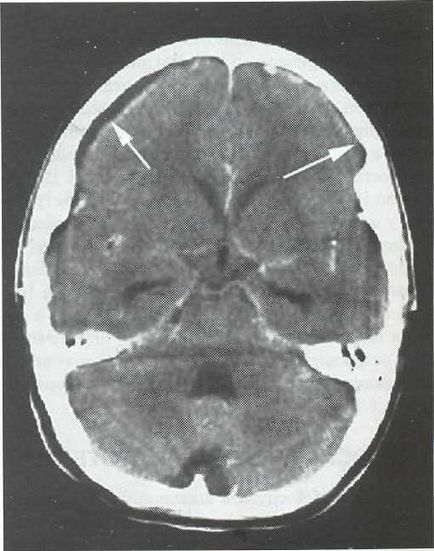

EDS diagnózist CT vagy MRI. Amikor CT EDS látható, ahol a zóna csökkentett félgömb alakú plotnos-ti (ábra. 22-1). Edges gennyes felhalmozódást egyértelműen konturiruyutsya felerősített jel beadva szemben, amely kapcsolatban van a gyulladásos folyamatok Som-kagyló. Ödéma medulla-proyav a tömeges hatása a félgömb oldalán EDS (ábra. 22-2). Szubdurális gennygyülem egyes SLE-teák kétoldalú (ábra. 22-3).

Ábra. 22-3. CT a kontrasztfokozó RD, axiális szeletet. Bifrontalnaya szubdurális gennygyülem (bizonyítja nyilak).